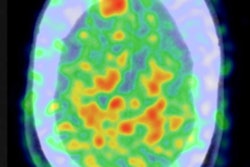

While PET/MRI may not be the optimum choice for head and neck cancer, adding a scan of the entire head to a routine whole-body PET/MRI protocol could reveal a significant number of incidental findings in the brain in asymptomatic cancer patients. A recent study found that MRI provides better resolution of brain tissue, and with metabolic information obtained from PET, the modality offers better characterization of both normal and abnormal brain findings in patients.